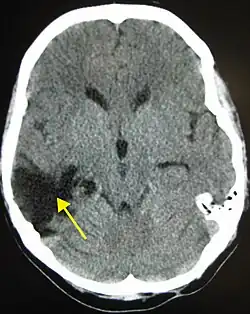

![]() | |

| CT scan showing cerebral contusions, hemorrhage within the hemispheres, and subdural hematoma. There is also displaced skull fracture of left transverse parietal and temporal bones.[2] | |